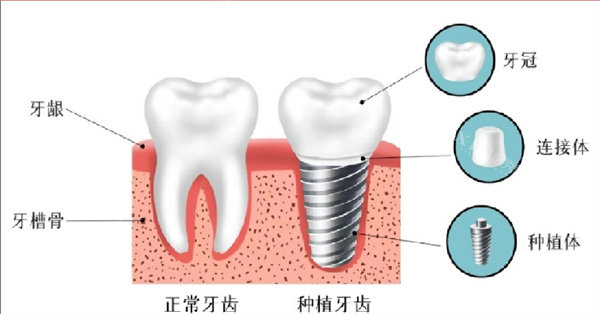

材料与工艺方面,春立正达种植体选用了符合GB/T 13810标准的纯钛(TA4G)或钛合金(TC4ELI)材质。这类材料具有良好的生物相容性,能够与人体组织协调共存。在表面处理工艺上,产品采用了喷砂酸蚀或阳极氧化技术,这种处理方式有助于促进种植体与骨组织的结合结果。从理化性能指标来看,产品达到了行业通用标准要求,为临床使用提供了基础支持。

设计与功能特性是春立正达种植体的另一优势所在。产品融入了骨控制设计理念,通过十字锁合与锥形连接结构的组合,提升了种植体在颌骨中的初期稳定性。这种设计特点使其能够适应不同骨质条件,对于骨质较为疏松的情况表现尤为突出。产品设计还考虑了即刻负重的临床需求,为患者提供了更多治疗选择。